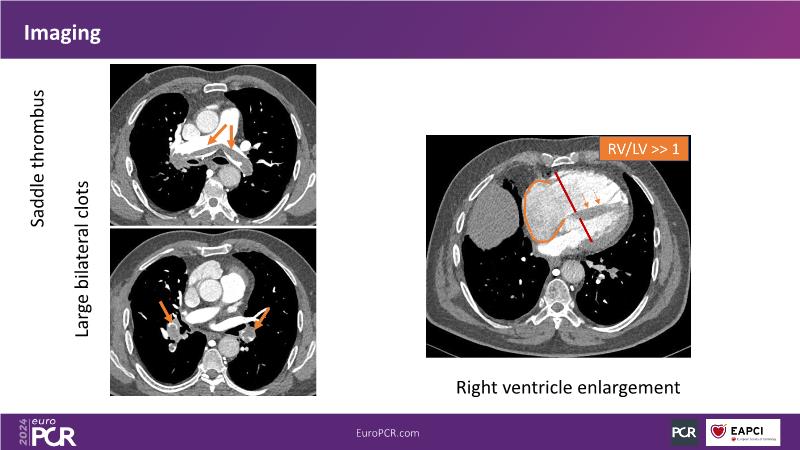

Join this session to delve into innovations in computer-assisted vacuum thrombectomy for acute pulmonary embolism, leveraging real-life case scenarios to share practical experiences and discuss treatment strategies. Amidst the current surge in scientific research, ongoing trials like STORM PE and STRIKE PE are pivotal in shaping the landscape of pulmonary embolism management.

- To share practical experience using real-life case scenarios